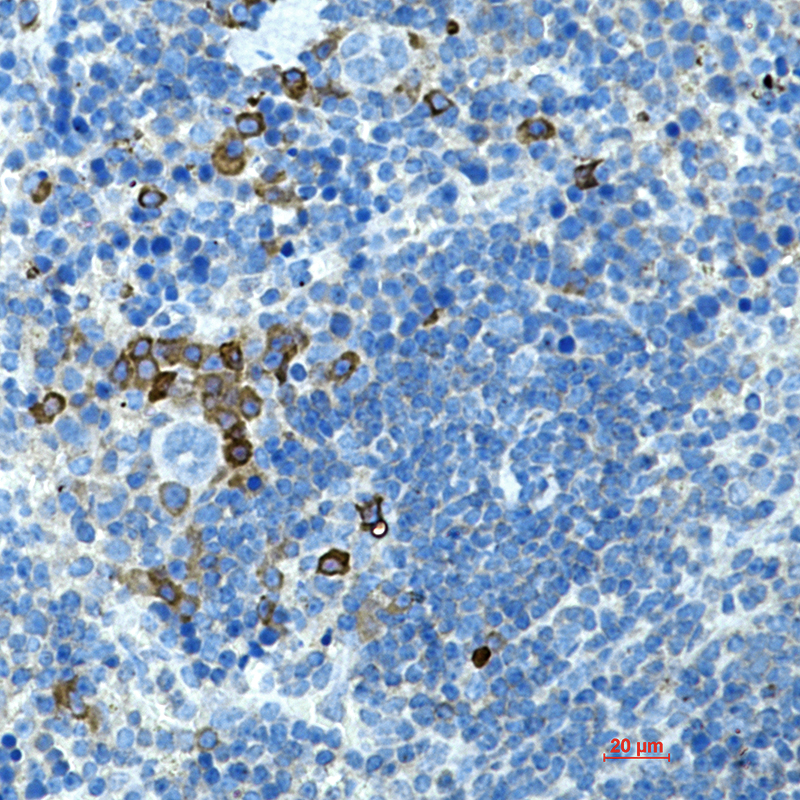

- Immunohistochemistry analysis of paraffin-embedded mouse spleen using CD272 antibody.High-pressure and temperature Sodium Citrate pH 6.0 was used for antigen retrieval.